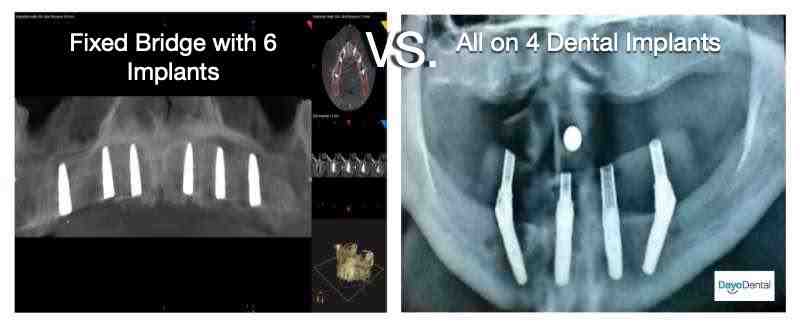

What are the three main types of dental implants?

Three implants

- Endosteal Implants. Endosteal implants are the most common dental implant and are attached directly to the jaw, as an alternative to permanent dental prostheses or bridges. …

- Subperiosteal Implants. …

- Mini-Dental Implants.